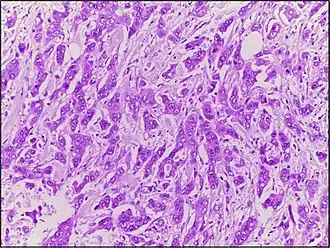

Carcinome canalaire

Les carcinomes canalaires sont une classe de tumeurs solides de la Classification internationale des maladies oncologiques. Elles sont développées aux dépens des canaux excréteurs d'une glande exocrine : sein, pancréas, prostate, glandes lacrymales...